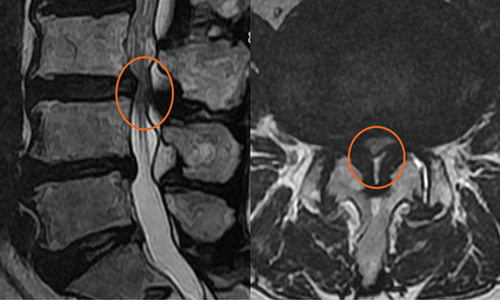

실제 척추 수술 사례

환자 : 65세 여성

증세 : 제 3,4번 요추간 돌출된 디스크와 비후된 황색 인대

경과 : 돌출된 디스크와 황색 인대가 제거된 결과, 비정상적인 신경의 신호가 하얗게 호전